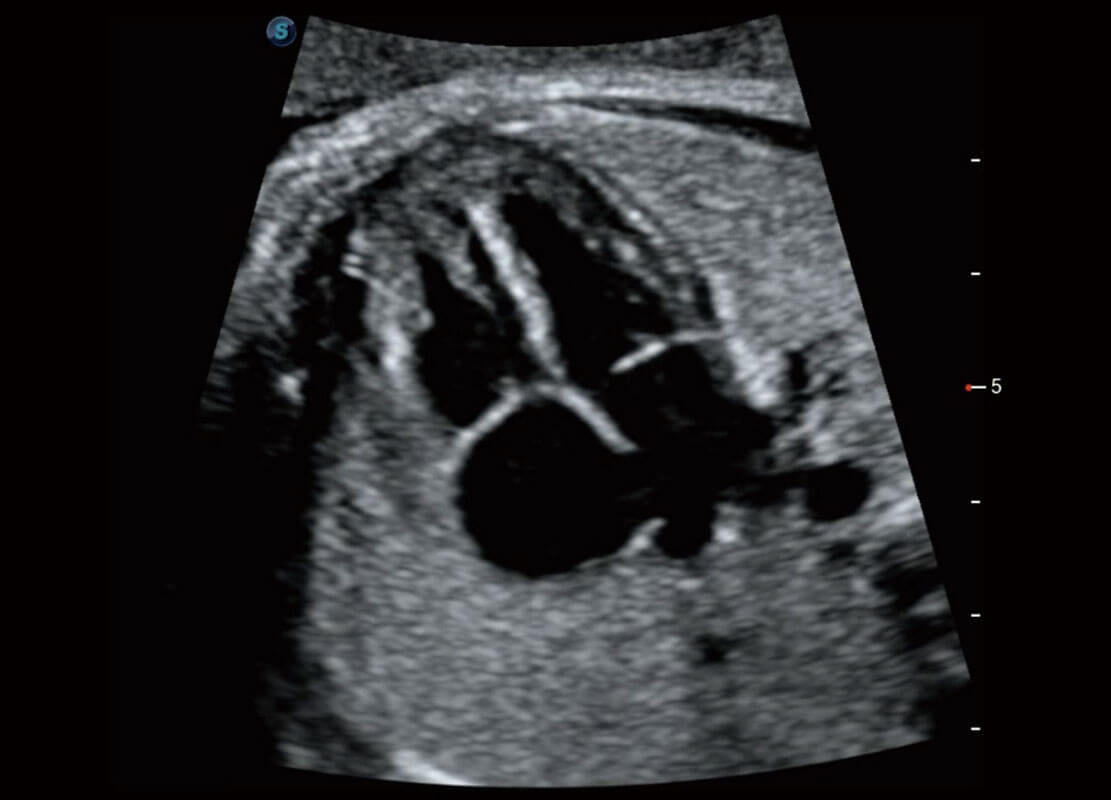

P60搭载一系列胎儿心脏成像技术,实现精细的胎儿心脏评估。

右室双出口